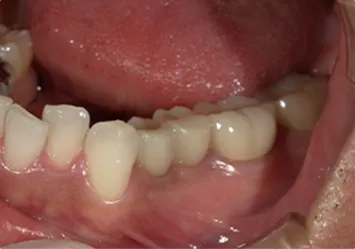

治療前

治療前写真 恵比寿南DENTAL 治療前写真 恵比寿南DENTAL

施術内容

【20代女性】

右下7番の歯根破折してしまい保存不可能となってしまった歯を抜歯し、インプラント埋入

治療期間

5ヶ月

リスク

術中の不可抗力によるトラブル(出血など)、術後注意事項を守らないことによる疼痛、感染、上部構造装着後口腔内清掃を怠ったことによるインプラント周囲組織の炎症

副作用

治療後の口腔内清掃、及びメインテナンスを怠ったことによるインプラント周囲粘膜炎またはインプラント周囲炎

費用

インプラント埋入:30万円

ジルコニアクラウン:12万円